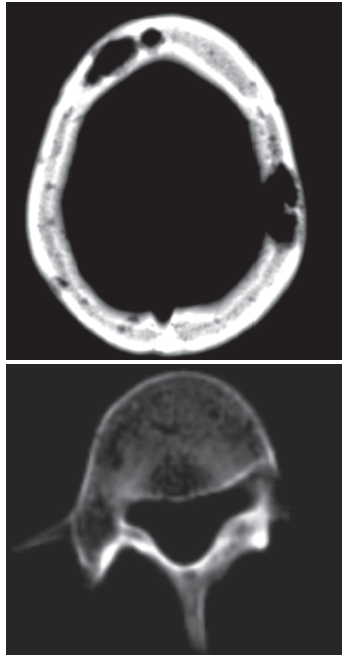

The patient had mild leukocytosis, anemia, and corrected calcium level of 11 mg/dL. Cerebrospinal fluid analysis yielded normal results. A brain CT scan showed multiple lytic lesions in the calvarium, with the largest in the left parietal bone. Abdominal CT revealed hepatosplenomegaly with low-attenuation lesions and scattered lucencies throughout the vertebral bodies.